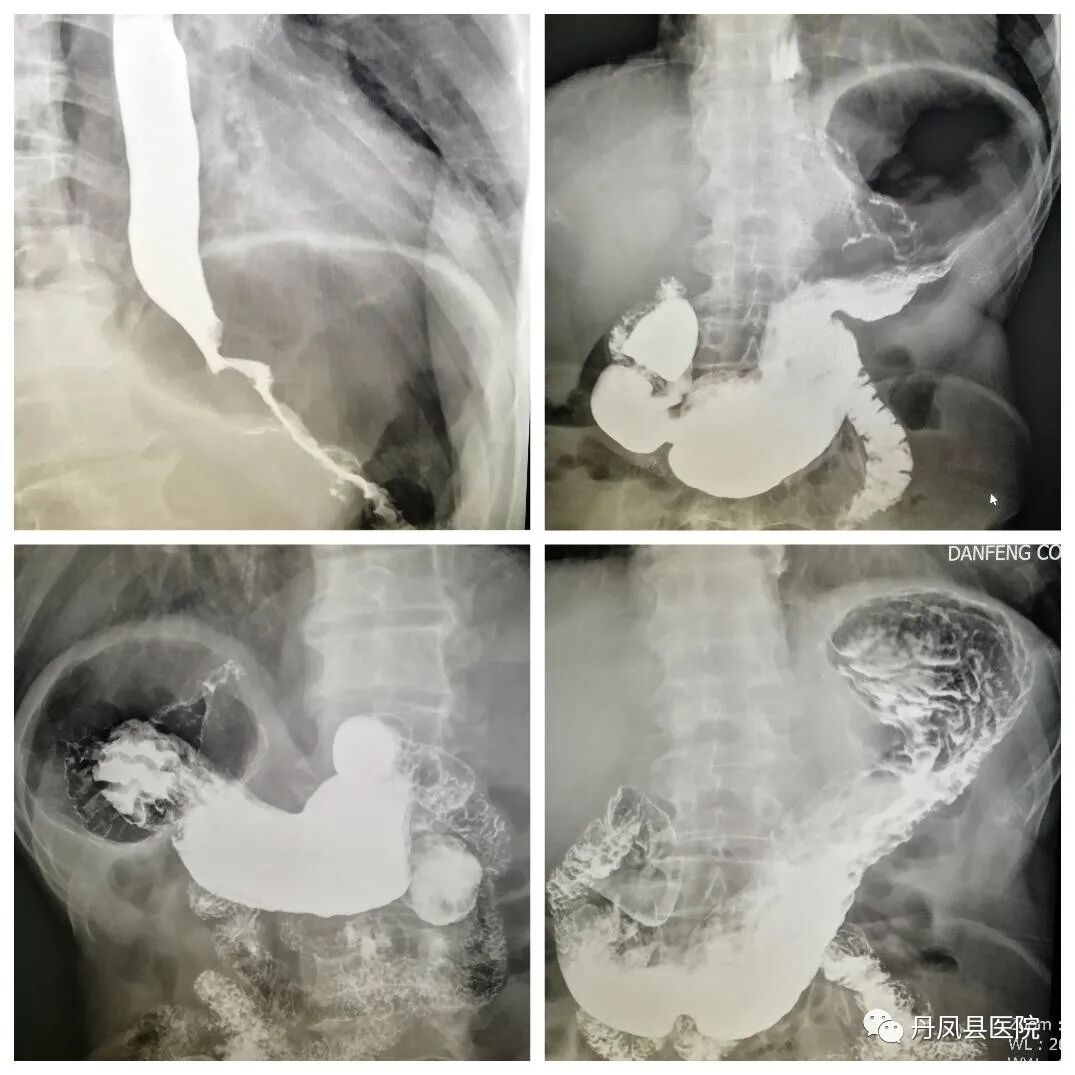

![上消化道.jpg]()

上消化道造影

![结肠造影.jpg]()

结肠气钡双重造影